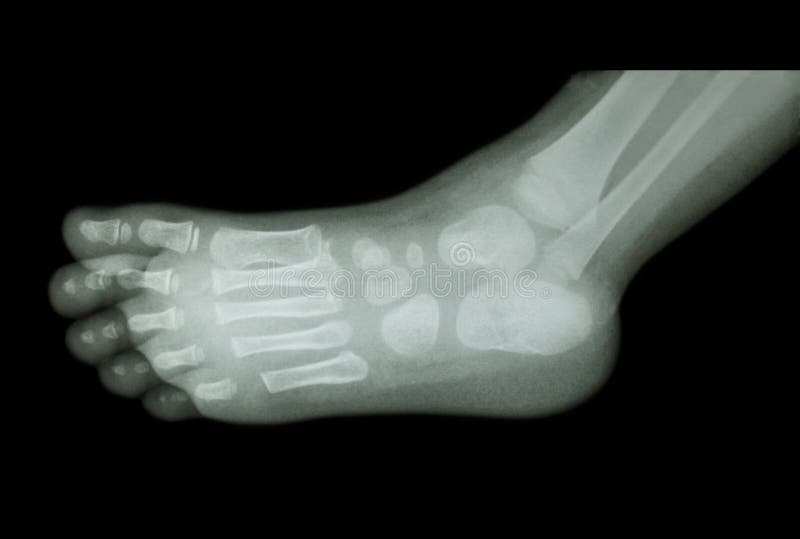

Child Ankle Xray Normal . Bony fragment at the tip of medial malleolus suggestive of secondary center. a broken ankle, also called an ankle fracture, is a common childhood injury. ottawa ankle rules: this is a repository of normal pediatric bone xrays and their examples for a quick reference look. Ankle fractures in children are most likely to involve the tibia and fibula (the. See the annotated images below from wikifoundry, and thanks also to radiopaedia: It should be noted, though, that in some countries, including the uk, only the mortise and lateral are used. Xrs are indicated if any of the following criteria are met. ankle radiographs are frequently performed in emergency departments, usually, after trauma, the.

NORMAL PEDIATRIC BONE XRAYS

film xray foot AP show normal child's foot Stock Photo 77257569 Alamy Child Ankle Xray Normal It should be noted, though, that in some countries, including the uk, only the mortise and lateral are used. a broken ankle, also called an ankle fracture, is a common childhood injury. See the annotated images below from wikifoundry, and thanks also to radiopaedia: ottawa ankle rules: this is a repository of normal pediatric bone xrays and. Child Ankle Xray Normal.